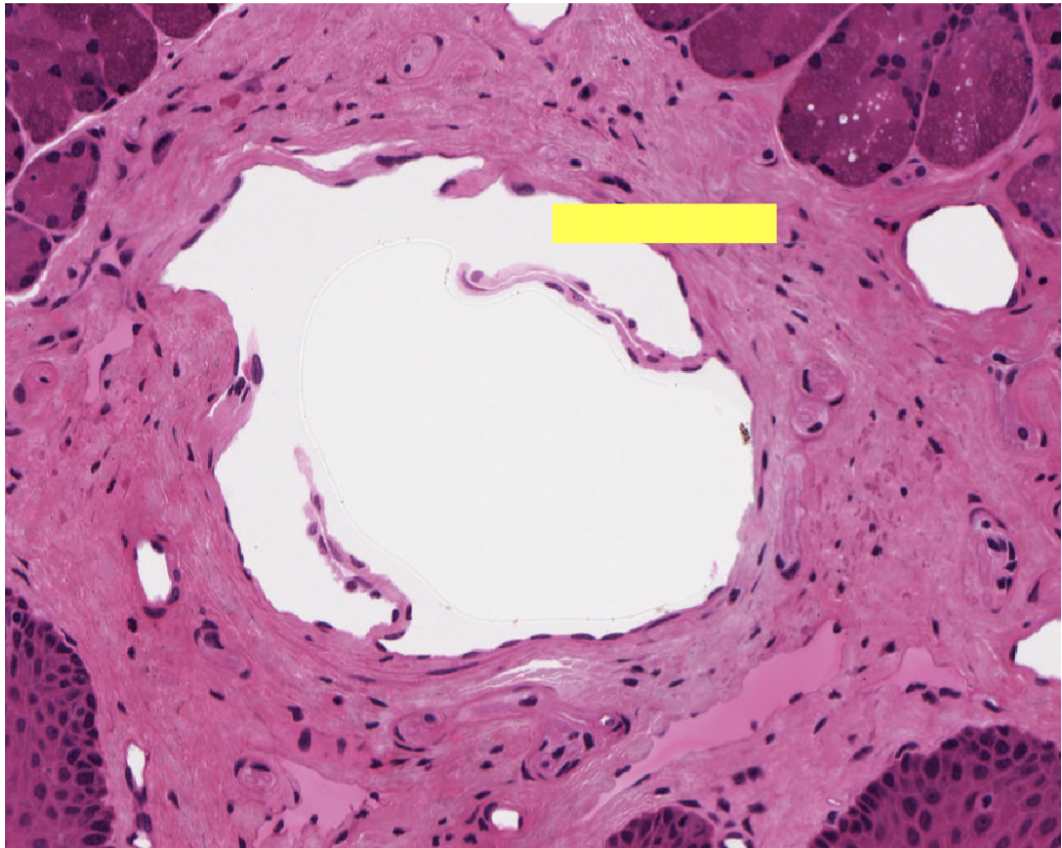

where in the body are we

where in body